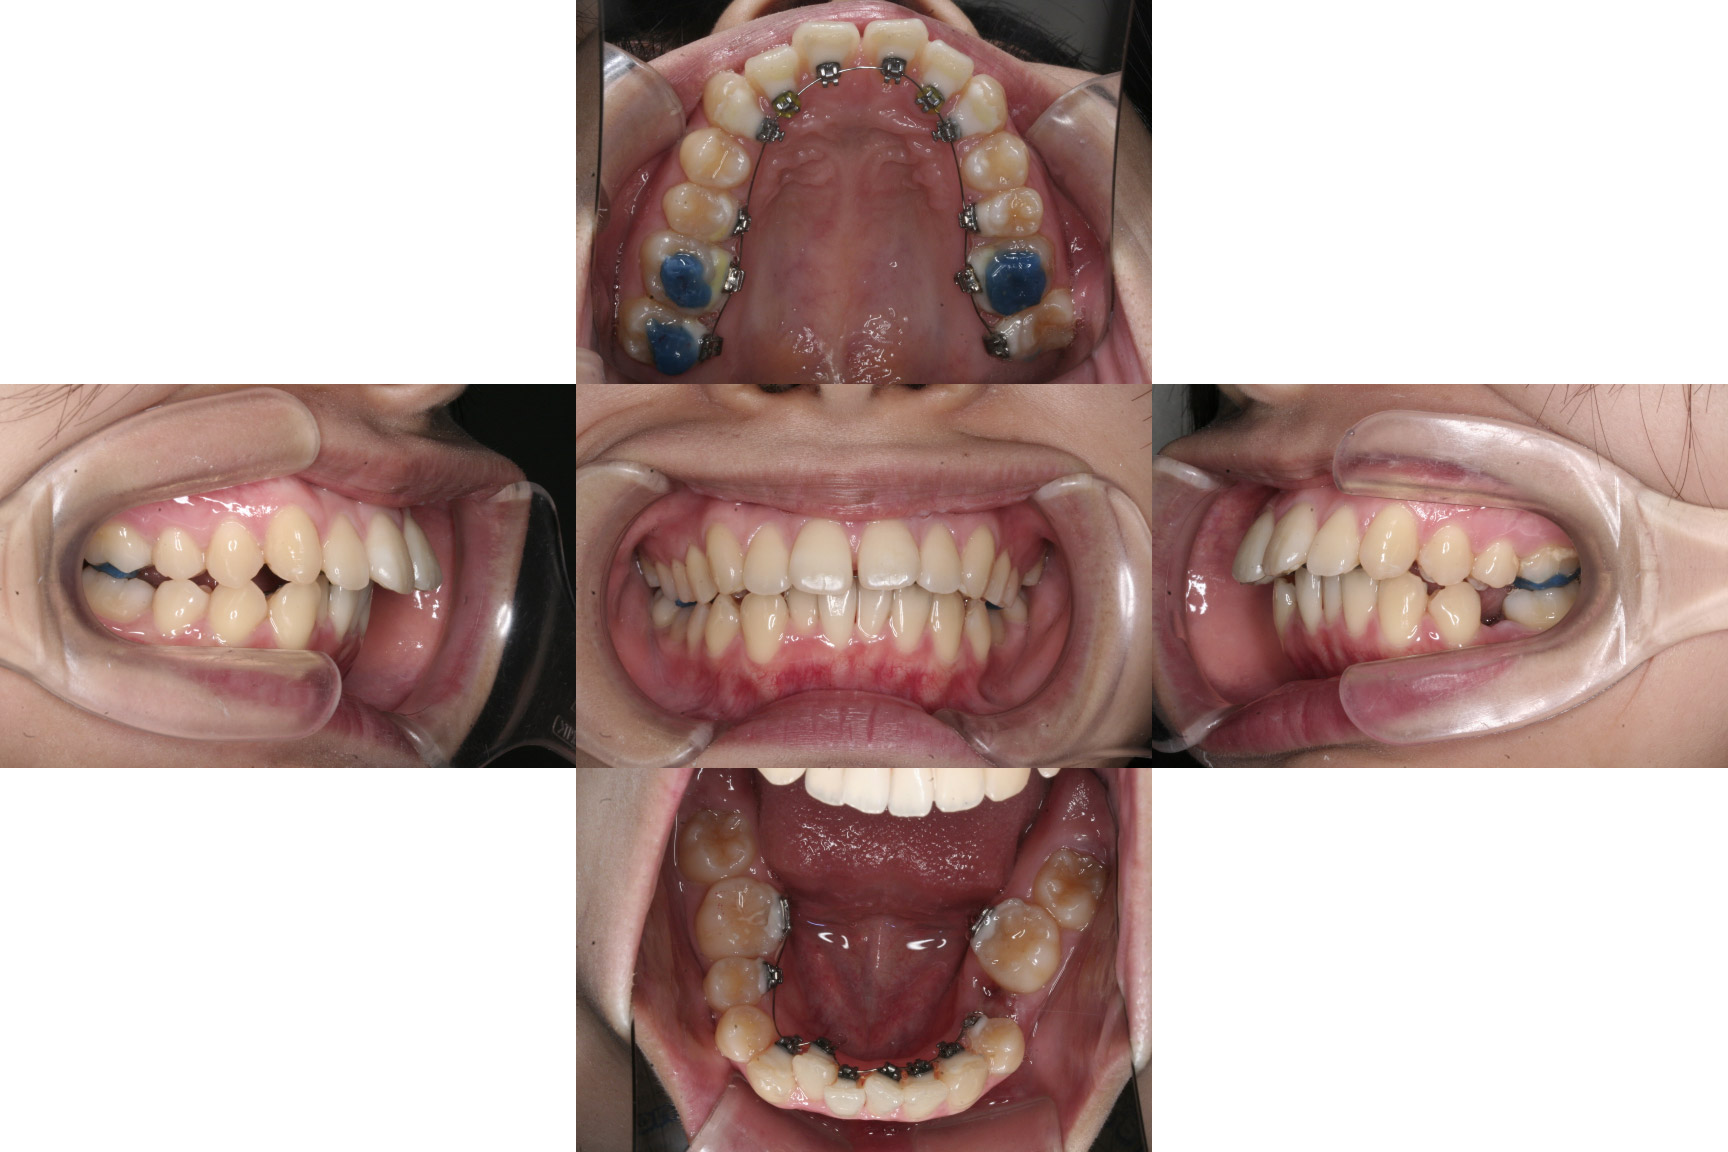

1年経過